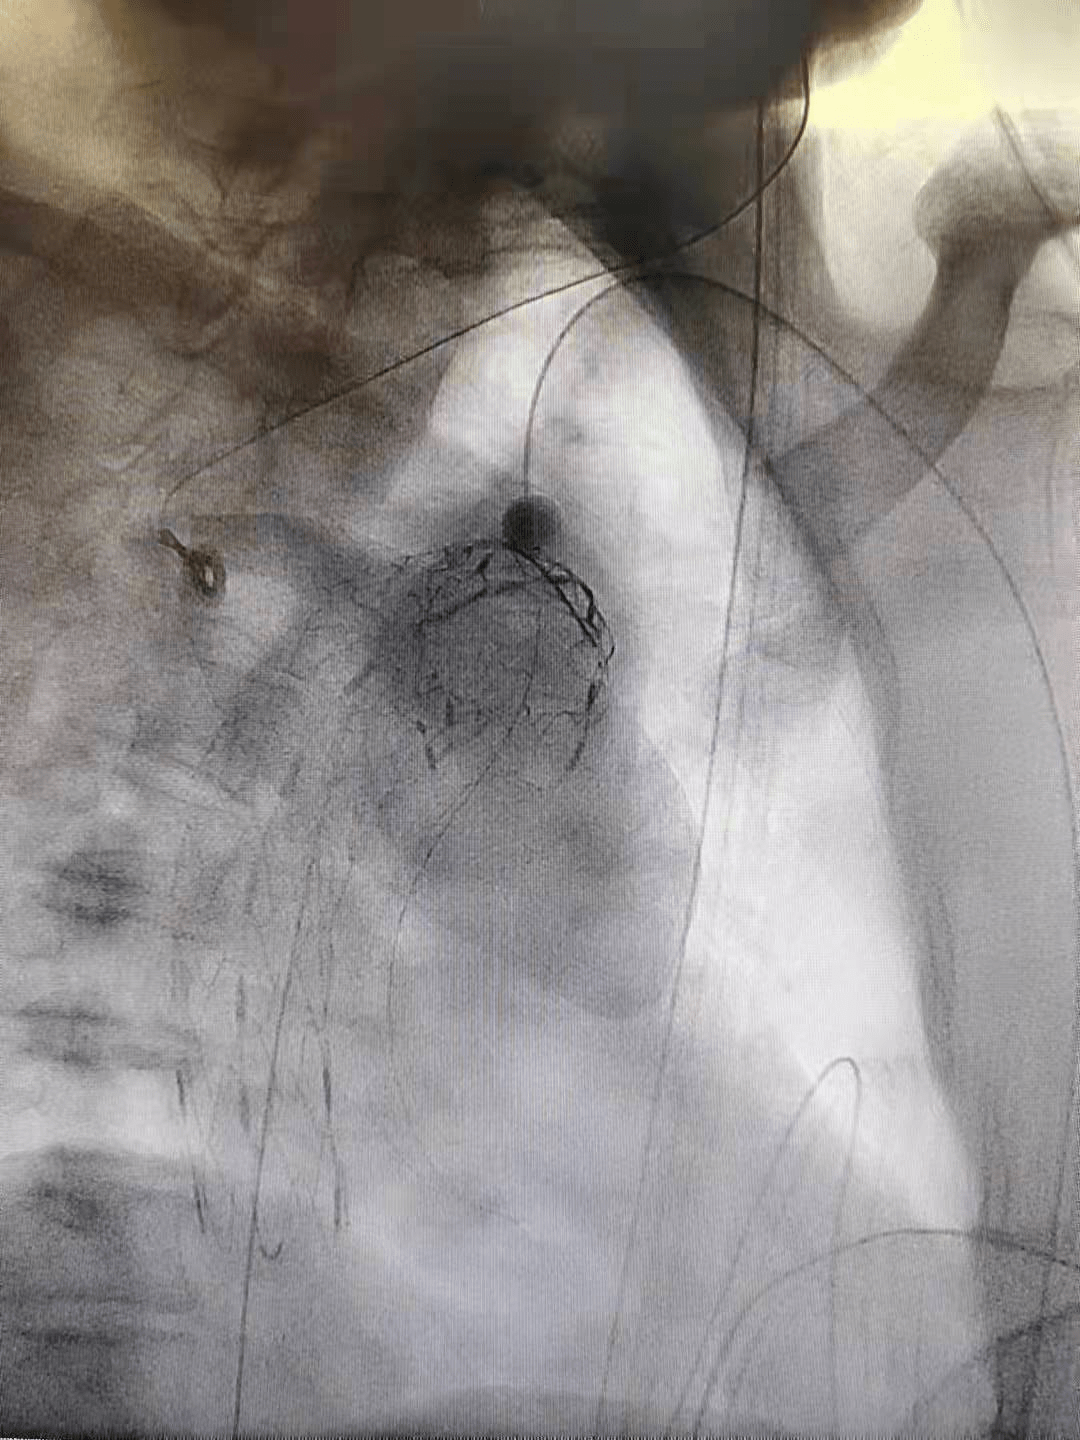

【团队|罕见又危险!巨大溃疡长在主动脉上!人民医院专家团队通力合作让患者转危为安】近日 , 一名肿瘤患者在天津市人民医院住院治疗期间 , 被发现体内存在罕见且极其危险的情况——主动脉弓上有一个巨大溃疡(见图一) , 随时可能破溃引发大出血!该院血管病诊疗中心血管2科刘洪主任团队果断采用“主动脉覆膜支架腔内隔绝+体内原位开创技术”贴合溃疡 , 成功为患者解除危机 。

(图一)

这名患者在市人民医院接受常规胸部强化CT检查时 , 被发现主动脉弓管壁增厚 , 在靠近左锁骨下动脉起始部的大弯侧有一处溃疡 。 得知患者情况后 , 刘洪主任紧急开展会诊 , 确诊这是“主动脉弓溃疡” 。

临床上 , 主动脉弓溃疡非常罕见 , 是主动脉内膜动脉粥样硬化以及斑块破裂后形成的溃疡 。 而这一病例更为罕见在于 , 溃疡面积巨大 。 “患处的血管直径从37.29毫米逐渐缩小 , 而我们测量到的溃疡范围至少有20.85毫米乘以10.71毫米 , 差不多一个成年人的大拇指肚那么大 。 ”刘洪主任解释说 , 大家都知道溃疡是皮肤或黏膜表面的溃破 , 但血管壁也就几毫米厚 , 溃疡的出现很容易导致凶险的主动脉夹层形成 , 并且随时可能引发血管破裂导致大出血 , 危及生命 。